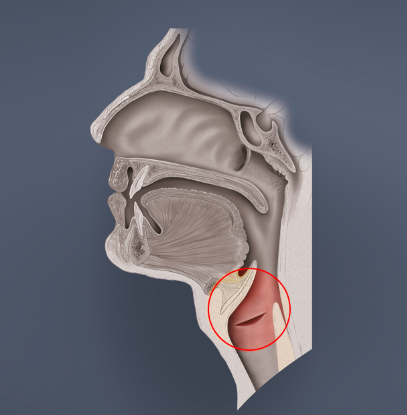

- Glottis (Stimmritze, engl. glottis)

Die Stimmritze stellt den Hohlraum zwischen den am Stellknorpel befestigten Stimmbändern dar und ist mit der Lunge und der Mundhöhle verbunden.

- Glottis

Die Glottis kann entweder ganz geöffnet, fast geschlossen oder ganz geschlossen sein.

Strecke Deine Zunge heraus und atme mit weit offenem Mund durch diesen ein und aus. Fühle, dass die Stimmritze nun offen ist.

Sage mit geöffnetem Mund „Aaaaaaahhhhhh“ und atme dabei durch den Mund ein und aus. Bei dieser Übung ist die Stimmritze durch die schwingenden Stimmbänder fast geschlossen.

Strecke die Zunge heraus, atme durch den Mund ein und halte danach die Luft an. Fühle, dass dabei Deine Stimmritze beim Luftanhalten schließt und vollständig geschlossen ist.

Einatmung

Luft anhalten